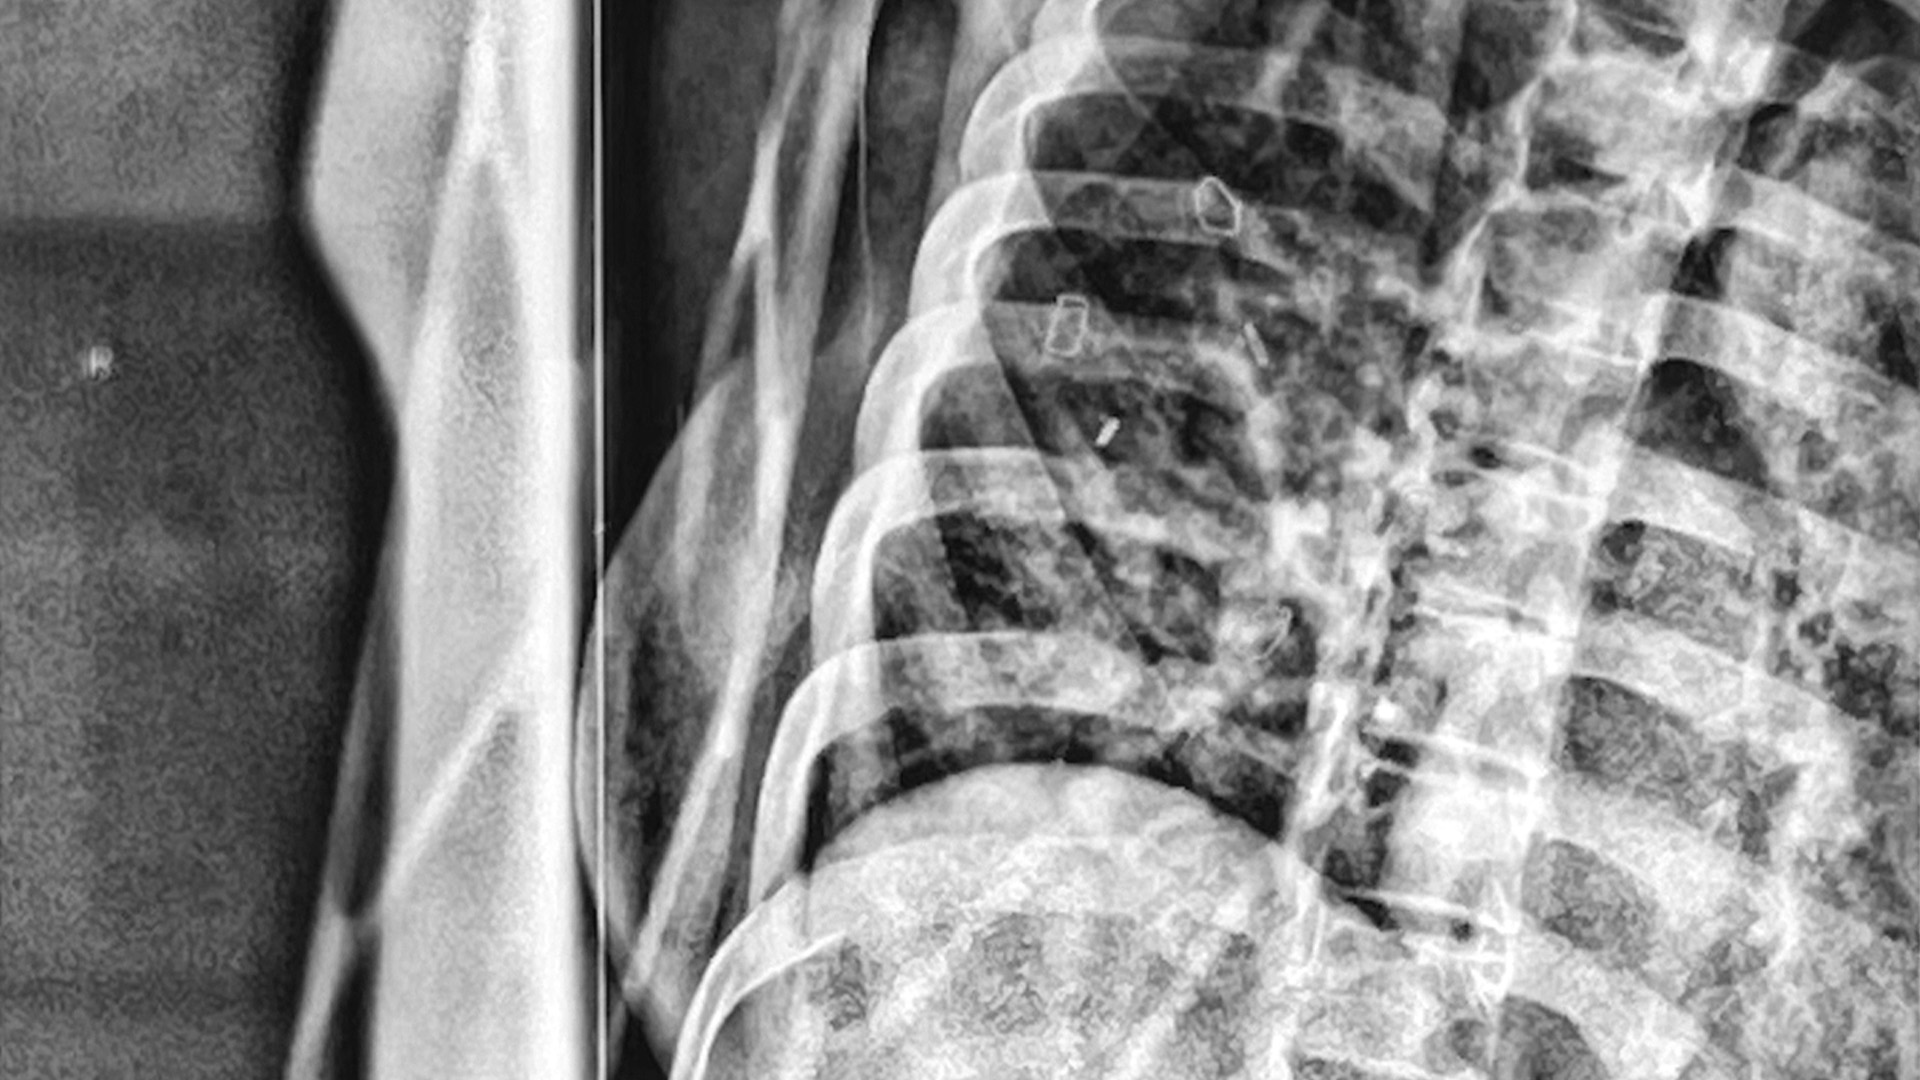

Digt om mit forløb med DCIS - Forstadie til brystkræft.

At få beskeden om et forstadie til brystkræft (DCIS) rystede mig. For at finde mening og skabe ro i tankerne begyndte jeg at skrive dagbog.